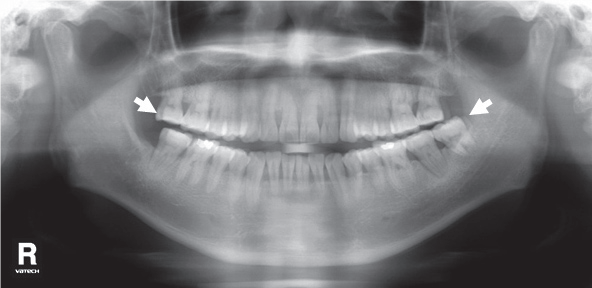

2. Наложение темной тени на верхушки зубов верхней челюсти.

Рис. 2. Наложение темной тени на верхушки зубов верхней челюсти.

Возникает за счет проекции воздуха в ротовой полости.

Что делать:

- Непосредственно перед началом экспозиции попросите пациента поднять кончик языка к нёбу.